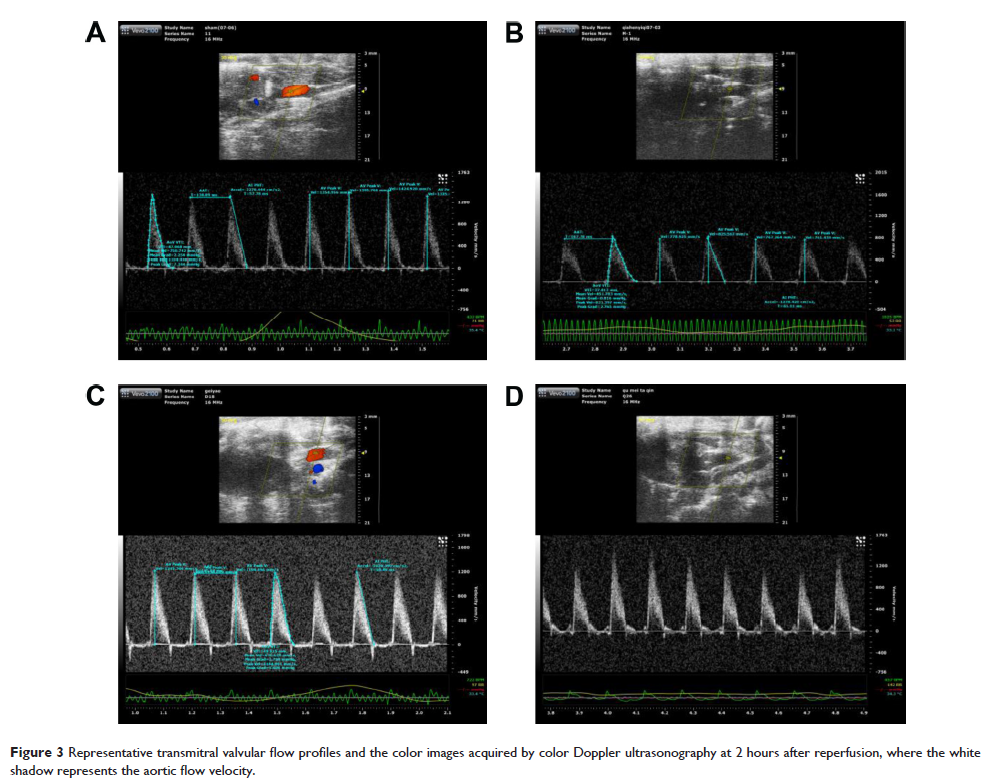

- 作者:Jiandang Zhou, Hui Huang, Shan Liu, Ping Yu, Qiquan Wan